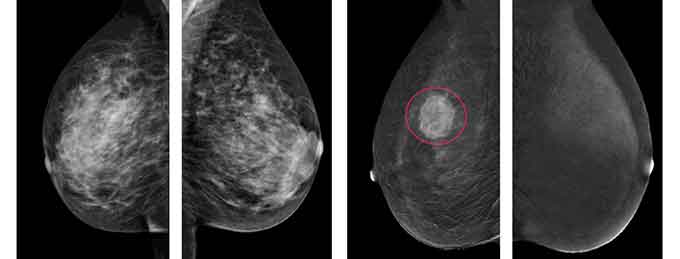

УЗИ не может заменить маммографию, но очень часто дополняет её. Врач УЗ-диагностики может прицельно осмотреть образование в груди со всех сторон, направляя ультразвуковые волны под разными углами, оценить кровоток и помочь ответить на вопрос: рак это или нет.

Ультразвуковая диагностика предоставляет возможность предварительно отличить доброкачественную опухоль от злокачественной, а также рассмотреть очаги патологии в тех местах, которые не видны на мамограмме (к примеру, в случае близкого их расположения к грудной клетке).

И УЗИ, и маммография – исследования, которые направлены на оценку состояния молочных желез. У многих пациентов возникает вопрос, почему одним назначают ультразвуковое исследование, а других отправляют на маммографию.

У каждого метода диагностики есть не только отличия, но и преимущества. К достоинствам УЗИ следует отнести:

- Безопасность процедуры для здоровья пациента, отсутствие болезненных ощущений.

- Возможность изучения состояния органа в режиме реального времени, под разными углами.

- Диагностика состояния лимфатических узлов.

- Исследование проводится, независимо от размера груди.

- Воспаления и патологии не являются противопоказанием к проведению исследования.

- По результатам можно оценить кровоток в железах и новообразованиях.

- Точность исследования – 90%.

Кроме того, в ходе УЗИ врач может с легкостью определить место взятия пункции.

Однако, у ультразвукового исследования есть ряд недостатков, к которым следует отнести отсутствие возможности определить качество новообразования. Для того чтобы получить более точные результаты, требуется использование инновационного дорогостоящего оборудования; кроме того, на результат влияют опыт и квалификация лечащего врача.